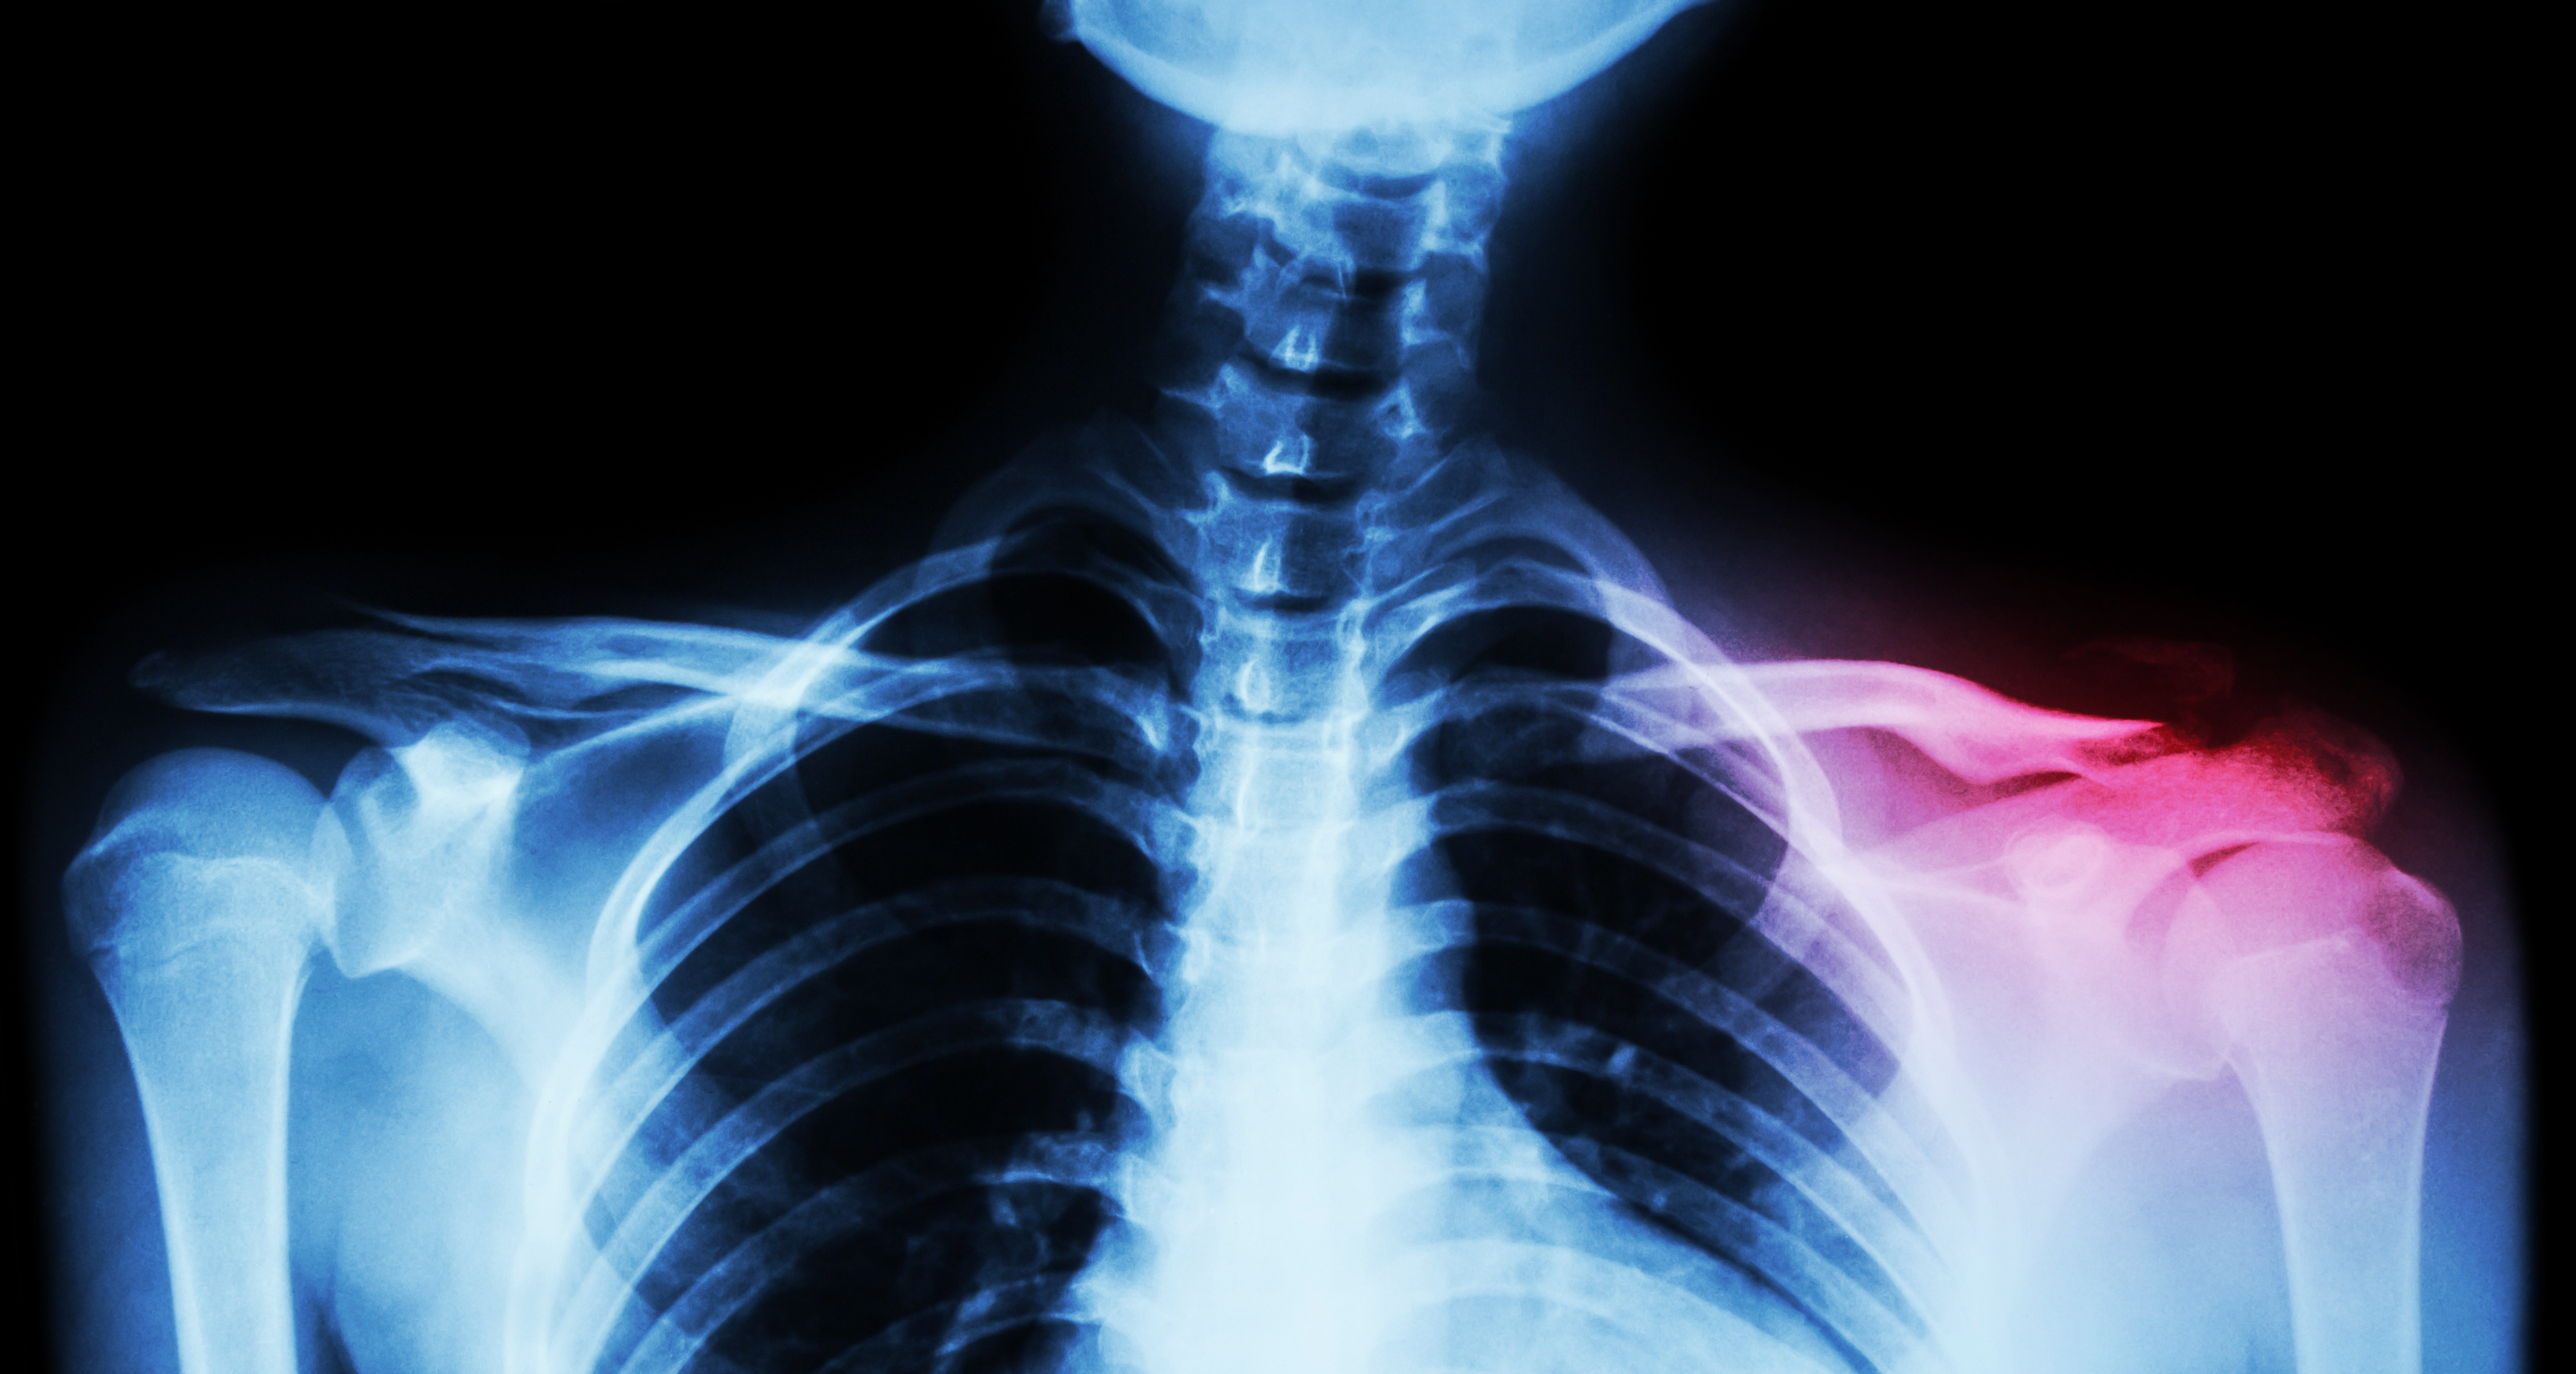

Shoulder pain, clavicle trauma, collarbone and acromion fracture Pain Under My Clavicle Collarbone pain can be caused by injuries, infections, health conditions, and even certain sleeping positions. The common cause of collarbone pain is an injury or fracture. Pain in the collarbone most likely occurs from a traumatic injury like a fracture, dislocation, or strain. At times, collarbone pain could be a symptom of a serious. Other common causes of clavicle pain. Pain Under My Clavicle.